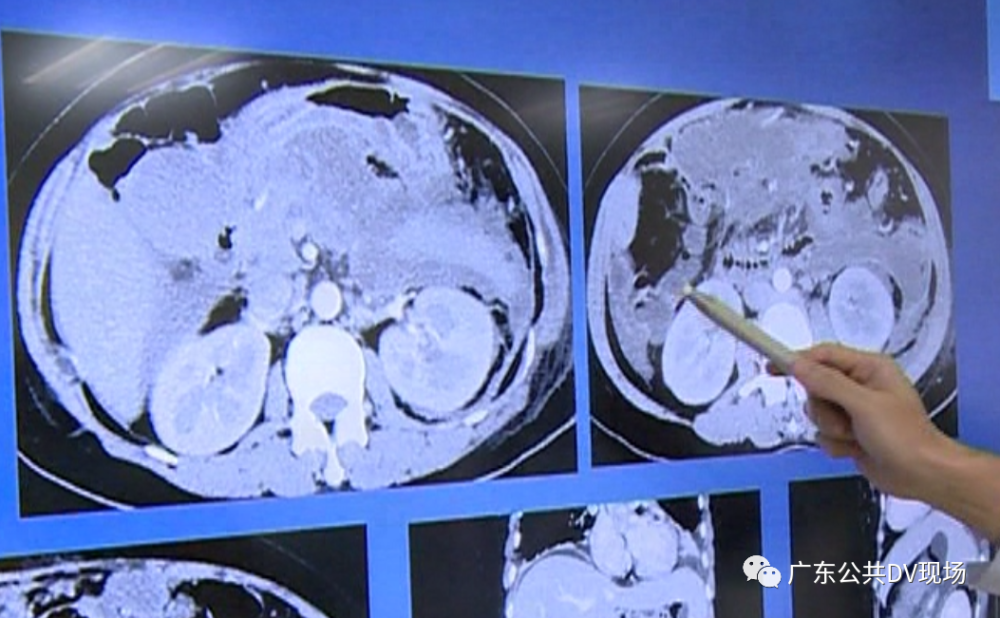

经过检查

阿文被当地医院医生诊断为

坏死性胰腺炎

同时伴胰腺内部出血

周围多发渗出等严重的状况

“处理起来非常棘手 , 胰腺炎、腹腔大量坏死;加重严重 , 渗出引流出来 。 ”